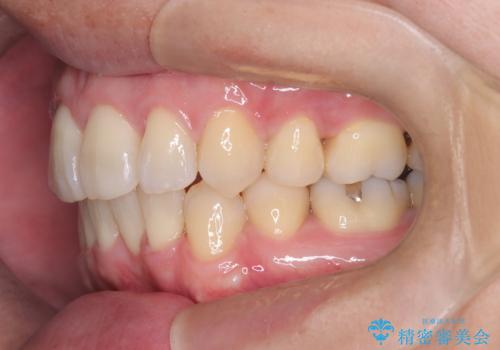

正面から見たときに右上2が全く見えないくらい、右上2が後ろに引っ込んでいる状態でしたが綺麗に並べる事が出来ました。

笑った時のスマイルラインもかなり綺麗になり大変ご満足いただく事が出来ました。

スムーズに治療を進める事ができ、2年2か月で治療をお終えました。

顔貌に対して歯の正中も合いました。